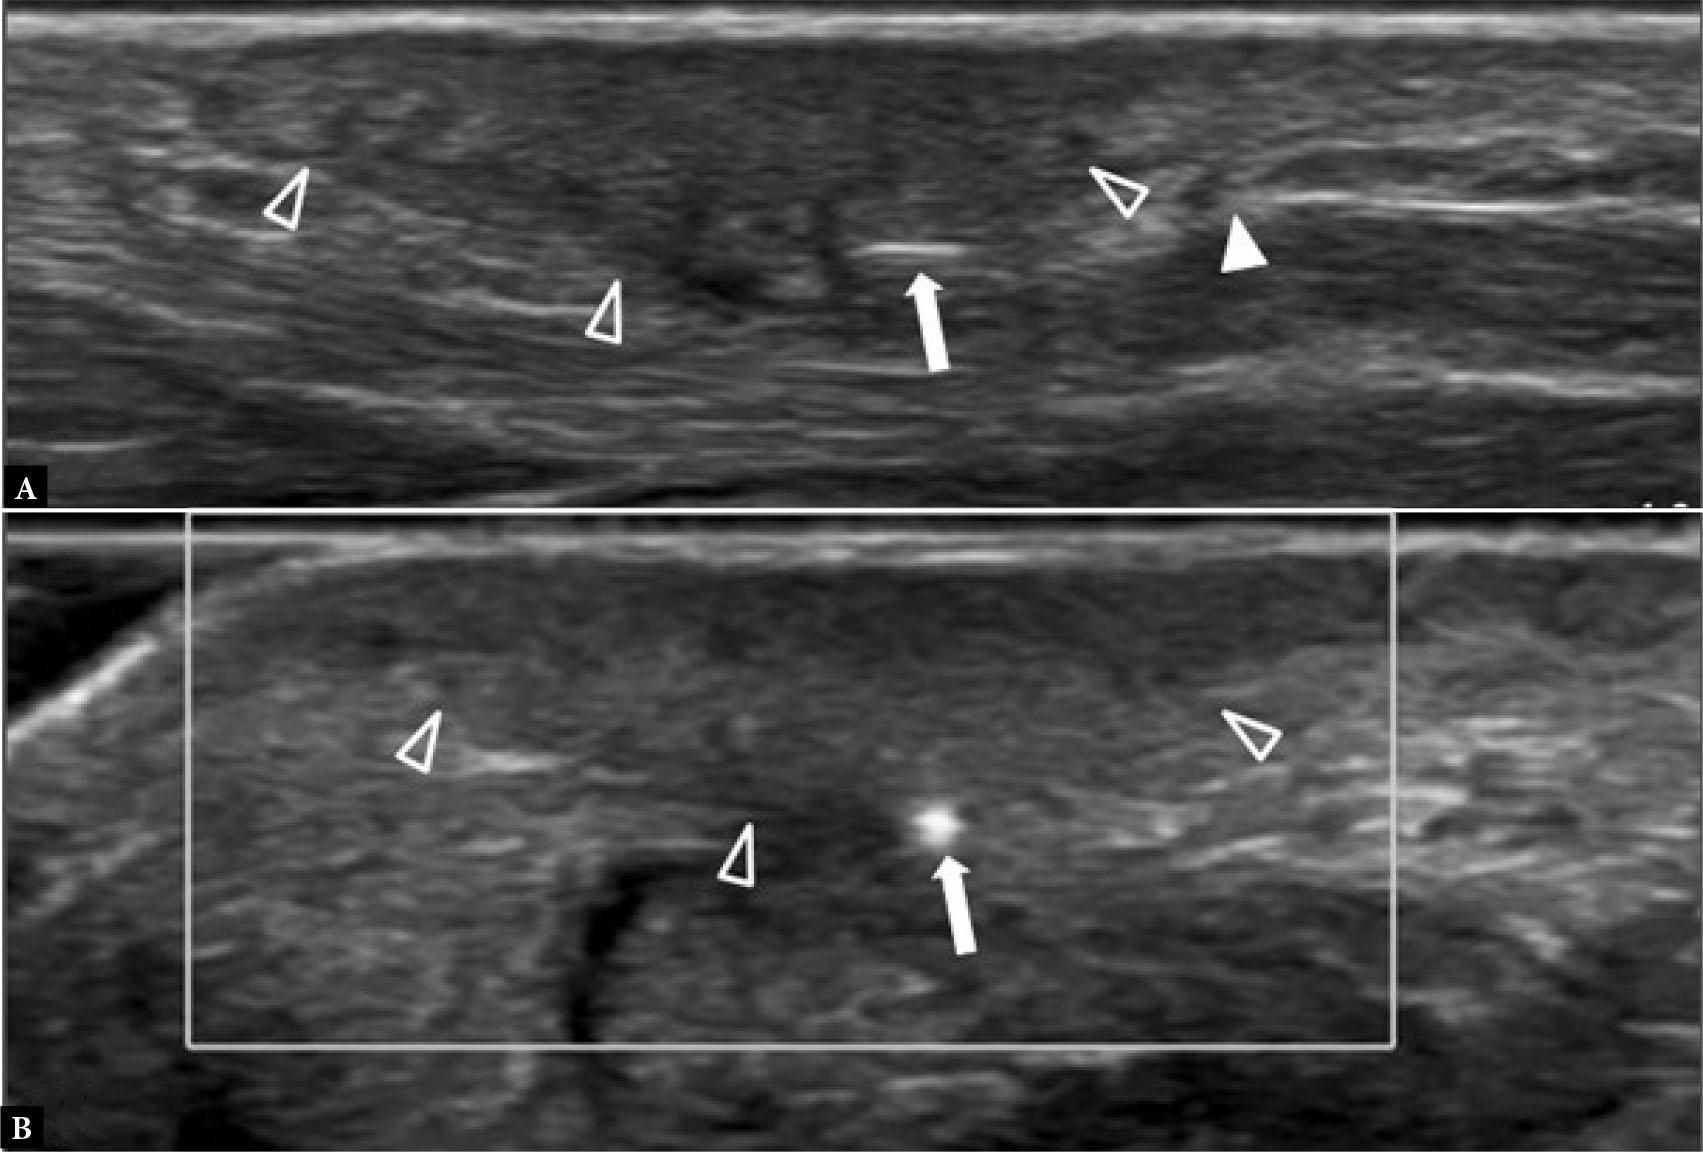

Stress fractures typically occur in young to middle-aged individuals undertaking unaccustomed high levels of exercise over an extended period. The 2nd and, less frequently, the 3rd metatarsal mid-shafts are commonly affected sites(1) (Fig. 1). The base of the 2nd metatarsal is splinted between the distal end of the medial cuneiform and the 3rd metatarsal bone. It is also a key weight-bearing bone, making it more susceptible to injury. The 1st, 2nd and 5th metatarsal bases, the navicular, cuneiform, cuboid, and medial sesamoid bones are additional common sites of stress fractures in the mid- and forefoot(1,2) (Fig. 2). Radiographs are normal in the earliest stages of stress fracture. US at this juncture may reveal a cuff of echogenic thickening due to thickened periosteum (‘periostitis’) around the cortex of the affected bone area. The cortex may be less distinct than usual, together with juxtacortical soft tissue edema and hyperemia (Fig. 1). While such findings are non-specific, they are usually diagnostic in the appropriate clinical setting without the need for additional imaging other than radiographic follow-up. MRI will provide even earlier detection of stress fracture than US, revealing focal bone marrow edema (BME) at the affected site, often with a thin hypointense fracture line(1) (Fig. 2). In the appropriate clinical setting, BME on fat-suppressed, fluid-sensitive sequences without a visible fracture line is termed a ‘stress reaction’ rather than a ‘stress fracture’(1). Radiographs and US will typically be normal in stress reaction. It is important to correlate any BME with clinical symptoms, as BME may occur due to physiological bone remodeling without necessarily being reflective of an injurious stress reaction(3).

Fig. 1.

41-year-old female with forefoot pain and swelling for one month. There was no specific traumatic event and no undue sporting activity. A tendon injury was suspected clinically A. Dorsoplantar (DP) radiograph shows normal 2nd metatarsal bone (arrowhead). B. Longitudinal greyscale and C. color Doppler, and D. transverse greyscale US images show moderate severity localized periosteal thickening (open arrow) of the 2nd metatarsal shaft dorsally, with moderate adjacent soft tissue thickening (open arrowhead) consistent with active stress fracture. E. Radiograph three months later showed marked periosteal thickening of the 2nd metatarsal shaft (arrow) compatible with healed stress fracture